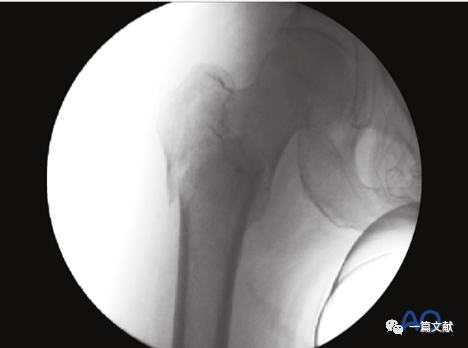

标准的侧位片如下图可见股骨干与头颈骨块的正常前倾角。

标准侧位片图像的解剖标记识别:1,大转子;2,股骨头;3,后缘线;4,前缘线;5,转子间线。

侧位片主要用来判断骨折复位情况及前倾角。但是,侧位片不是判断内固定位置的最佳选择,如下图: